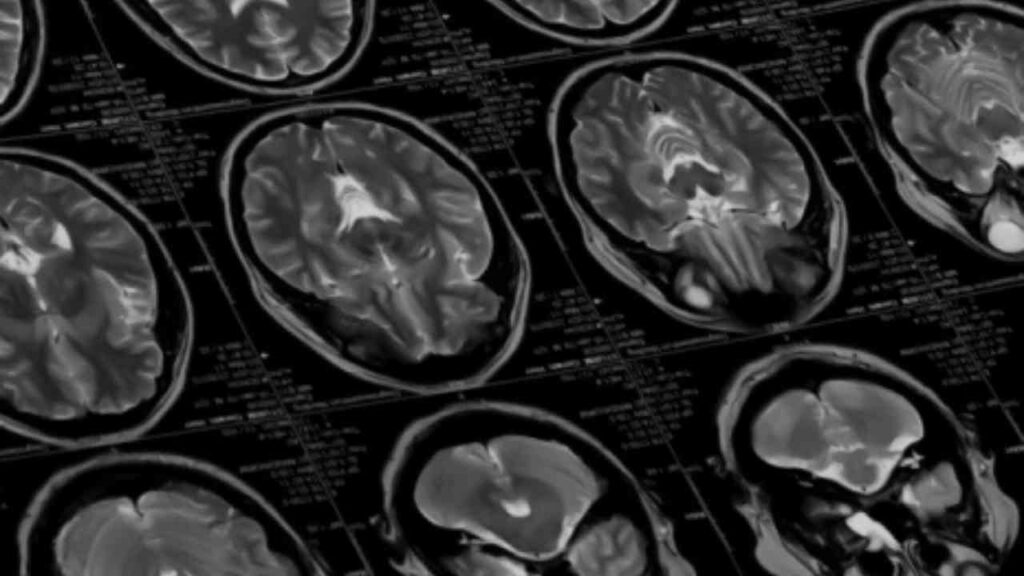

Boston. Ein Forscherteam am Massachusetts Institute of Technology (MIT) hat eine bahnbrechende Technologie vorgestellt, die das Potenzial hat, die Behandlung neurologischer Erkrankungen grundlegend zu verändern: Drahtlose Mikroelektronik, die über den Blutkreislauf ins Gehirn gelangt – ganz ohne chirurgischen Eingriff. Die Innovation könnte insbesondere bei Erkrankungen wie Alzheimer, Parkinson oder Epilepsie neue Perspektiven eröffnen.

Die Neurotherapie ohne Operation MIT basiert auf winzigen Chips (SWEDs – sub-cellular wireless electronic devices), die mit Immunzellen fusioniert und dann ins Gehirn transportiert werden. Diese Zell-Elektronik-Hybride überwinden die Blut-Hirn-Schranke und sammeln sich gezielt an entzündeten Regionen im Gehirn. Dort können sie drahtlos aktiviert werden – etwa durch nahinfrarotes Licht – und Nervenzellen gezielt stimulieren.

In Tierversuchen mit Mäusen zeigten die Forschenden, dass die Chips innerhalb von 72 Stunden im Zielgebiet ankamen. Die Aktivierung von Hirnzellen konnte präzise nachgewiesen werden. Laut Projektleiterin Deblina Sarkar entsteht damit „eine neuartige Schnittstelle zwischen Biologie und Technik“. Das Verfahren könnte nicht nur bei schwer zugänglichen Hirnarealen Vorteile bringen, sondern auch die Behandlungskosten und -risiken senken.